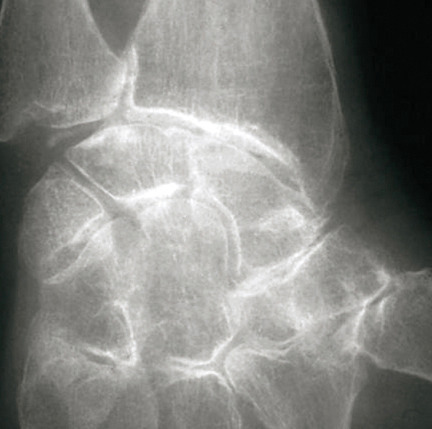

La forme pseudorhumatoïde est rare (5 %), simulant une polyarthrite rhumatoïde (diagnostic différentiel), avec parfois des signes systémiques d’inflammation (élévation de la vitesse de sédimentation et de la CRP). Le diagnostic repose sur la mise en évidence des cristaux de PPC. La radio peut mettre en évidence des calcifications des cartilages articulaires (fig. 6) et des fibrocartilages (fig. 7, 8, 9 et 10). L’échographie (plus sensible) peut mettre en évidence des dépôts de PPC, qui apparaissent comme une fine bande hyperéchogène au sein des cartilages hyalins et comme des points scintillants dans les fibrocartilages ou dans la membrane synoviale. Dans l’arthrite chronique à PPC, lespossibilités thérapeutiques sont, par ordre de préférence : colchicine (de 0,5 à 1 mg/j), petites doses de cortisone, parfois les AINS per os (mais leur prescription est souvent limitée par les comorbidités chez les patients âgés), méthotrexate et l’hydroxychloroquine. Il n’y a pas aujourd’hui de traitement « de fond », mais des molécules sont à l’étude.